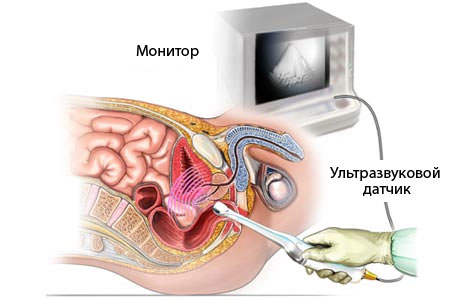

Проводити його можуть двома способами:- абдомінальним - датчик встановлюється на стінку живота,

- вагінальним - датчик вводиться у внутрішній статевий орган.

З попередньої бесіди з пацієнткою лікар визначає, який метод діагностування їй краще призначити. Підготовка до УЗД при вагітності для проведення звичайним способом (абдомінальним) полягає в наступному: за півгодини до обстеження випивають 500 мл води для наповнення сечового міхура. Кишечник також необхідно підготуватися до звільнення кишечника від газів для максимально точного результату. За день чи два утриматися від вживання таких продуктів, як газовані напої, капусти, винограду, насіння, горіхів, чорного хліба.

Для обстеження вагінальним способом діагностики вагітної потрібно прийняти душ, звільнити сечовий міхур від води. Молода мама повинна бути спокійна. При зайвої емоційної збудженості може підвищитися артеріальний тиск, для жінки і плоду, що розвивається в її організмі краще цього уникати, важливо спокійно підготуватися до необхідних процедур.